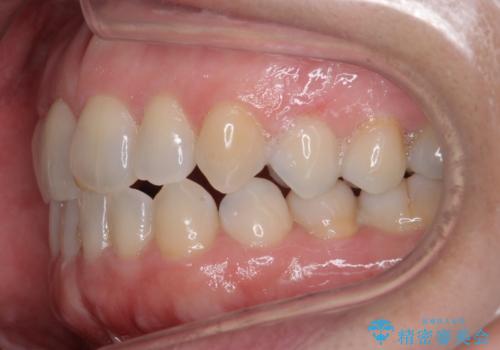

- 右上の2番目の前歯がとがった形をしていたため、セラミックで形を整えています。

短くてとがった歯の形が反対側と同じ形となり、左右対称となり、ずいぶん自然な印象になりました。

下の前歯とのかみ合わせが切端咬合だったため、前歯の部分矯正も併せて行っています。(費用別途)